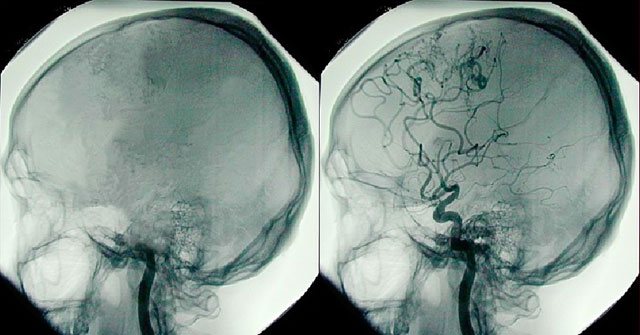

Ангиография – рентгенологический метод исследования, позволяющий визуализировать кровеносные сосуды мозга с помощью введения в них контрастных веществ. Само изображение получают с помощью компьютерной или магнитно-резонансной томографии.

Стандартное ангиографическое исследование, связанная с проведением обычных рентгеновских снимков, активно замещается на методы с использованием КТ и МРТ. Это позволяет повысить качество получаемых изображений, получить объемную карту сосудов головного мозга, кроме того, такие исследования более безопасны для пациентов.

Ангиография проводится в следующих ситуациях:

- подозрения на наличие артериовенозной мальформации и аневризм сосудов;

- необходимость оценки степени сужения просвета артерии в связи с ее стенозом или закупоркой тромбом;

- изучение строения сосудистого русла рядом с опухолевым новообразованием для планирования хирургического вмешательства.